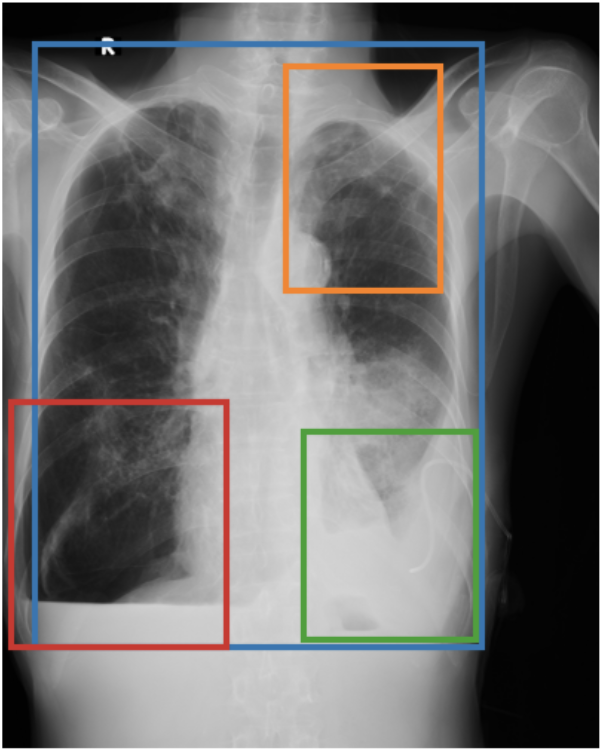

To address these drawbacks, state-of-the-art models such as MAIRA-2 [3] explicitly incorporate grounded report generation to better align local visual evidence with the textual findings. For example, MAIRA-2 is trained on a diverse set of localization-based tasks, including phrase grounding and grounded report generation. However, as shown in Figure 1, current models often exhibit a bias in which the target visual regions become overly associated with abnormal findings, leading to false positives in medical reports.

As shown in Table 1, our data composition reflects this imbalance: over 12.9M instances from Chest ImaGenome dominate the much smaller MS-CXR (815 PG instances) and PadChest-GR (12k instances) datasets. Beyond the imbalance between datasets, each dataset also exhibits substantial intra-dataset class imbalance. For example, anatomical regions in AGRG and semantic categories in PG are unevenly represented, leading the model to overfit frequent regions, neglect rare but clinically important ones, and hallucinate findings (Figure 1). Our curriculum framework addresses both sources of imbalance.